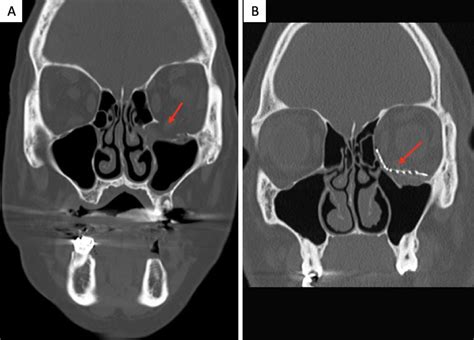

To accurately diagnose an orbital floor fracture, healthcare providers rely on a combination of physical examination and advanced imaging. During the physical exam, a surgeon will test the range of motion of your eyes and check for nerve sensation in the face. To confirm the diagnosis, the gold standard is a Computed Tomography (CT) scan of the orbits.

CT Scan (Coronal View) Best visualization of the orbital floor and sinus involvement.